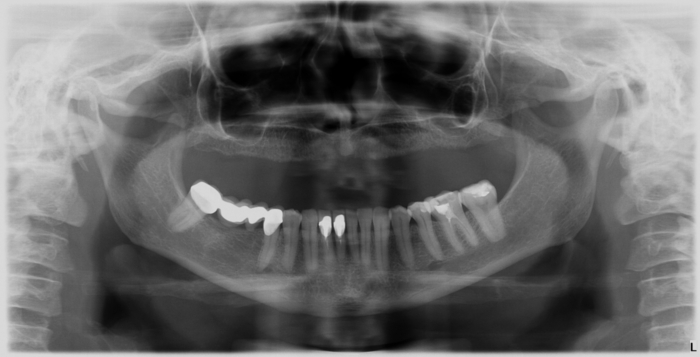

Raio-x Inicial